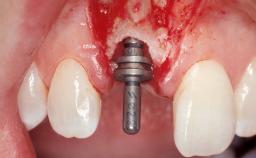

A 30-year-old female patient had lost tooth 21 and was referred to our clinic for consultation and treatment. Due to advanced apical infection, tooth 21 had been extracted two months earlier at another clinic and an acrylic-resin tooth had been bonded to the adjacent teeth. The patient desired implant treatment to avoid any damage to the adjacent natural teeth. While the patient had no history of any systemic disorder, she was a heavy smoker and exhibited medium to advanced periodontitis in the entire jaw. After the initial treatment to achieve a pocket probing depth of less than 4 mm and no bleeding on probing, a decrease in the height of the papillae mesial and distal to the extraction site and overall gingival recession were observed.

Type of Implants One-Piece|Reduced-Diameter

Bone Augmentation Horizontal|Staged

Augmentation Materials Autogenous chips|Membrane

Soft Tissue Grafting Simultaneous